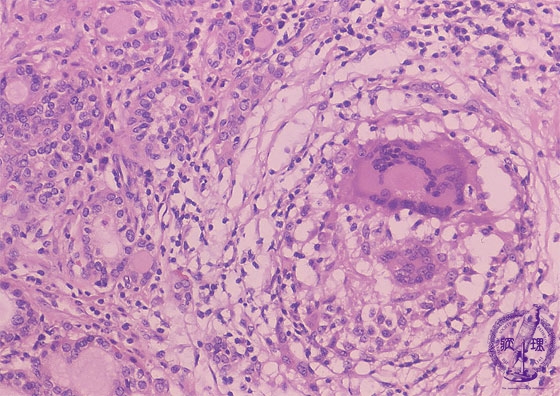

Microscopic findings (HE stain, high power view). Granulomas are composed of foreign body giant cells, epithelioid cells, and lymphocytes. Giant cells contained phagocytized colloid material.